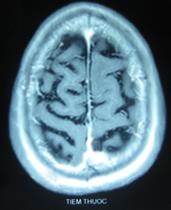

- Chụp CT sọ não: Hình ảnh khối u vùng đỉnh trái, kích thước 2×2 cm, có phù não rộng xung quanh

- Chụp CT lồng ngực: Hình ảnh khối u thùy trên phổi phải kích thước 2×3 cm

+ Kết quả chụp cộng hưởng từ sọ não: Khối u não vùng đỉnh trái, kích thước 1,7×2,3cm, có phù não xung quanh.

- Thực thể: khối u não di căn biến mất trên phim chụp cộng hưởng từ, u phổi nhỏ lại trên phim chụp cắt lớp vi tính.